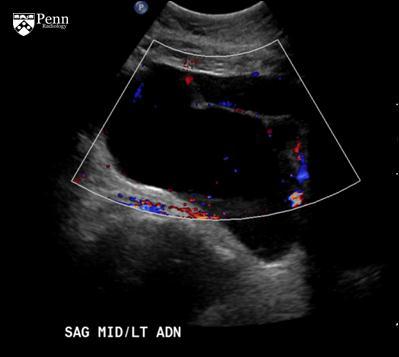

Peritoneal inclusion cyst

Imaging features

Ovary may lie in center of cyst, suspended by thin adhesions, like a spider in a web.

Ovary may be eccentrically located within the cyst, adherent to the cyst wall.

Ovary may lie within the cyst wall.

Adjacent ovary will be normal in appearance, though may be slightly distorted due to mass effect.

No enhancing components will be identified on contrast-enhanced CT or MRI; the adjacent normal ovary should not be confused with a mural nodule.

Low-resistance flow may be detected in septations on Doppler flow ultrasonography due to small vessels traversing the mesothelial tissue in the cyst walls.